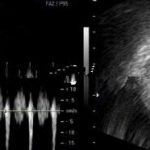

只要患上宫外孕,很多医院治疗唯一的办法就是做输卵管切除,对医生来讲即安全,又不留后患,但是再也不能怀孕了。 北京安太医院治疗宫外孕可进行3D腔镜下开窗取胚宫外宫内转移,继续妊娠,治疗异位妊娠。不切输卵管,同时寻找病因去除之!是宫外孕患者理想的治疗方案。